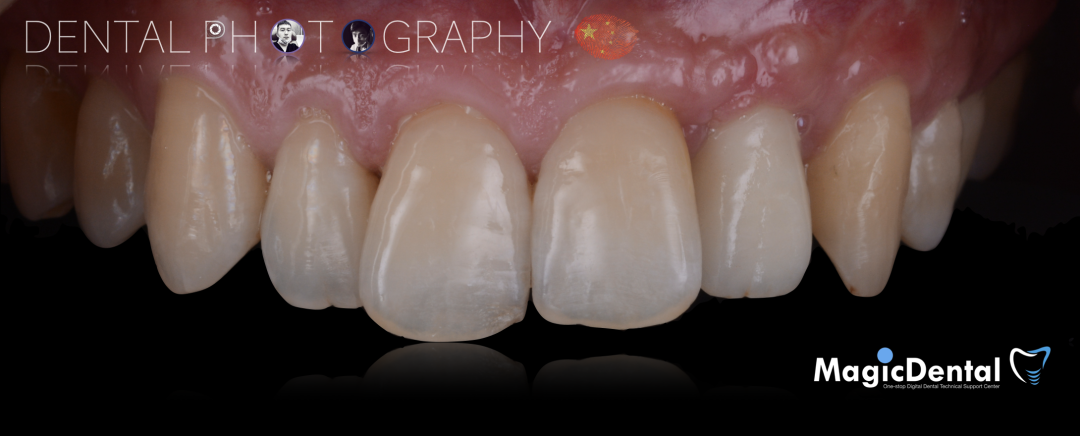

口外制作树脂临时冠,抛光。安放树脂修复的临时冠,调整正中、前伸、侧方均无咬合干扰。

术后三个月口内正面像

术前术后对比